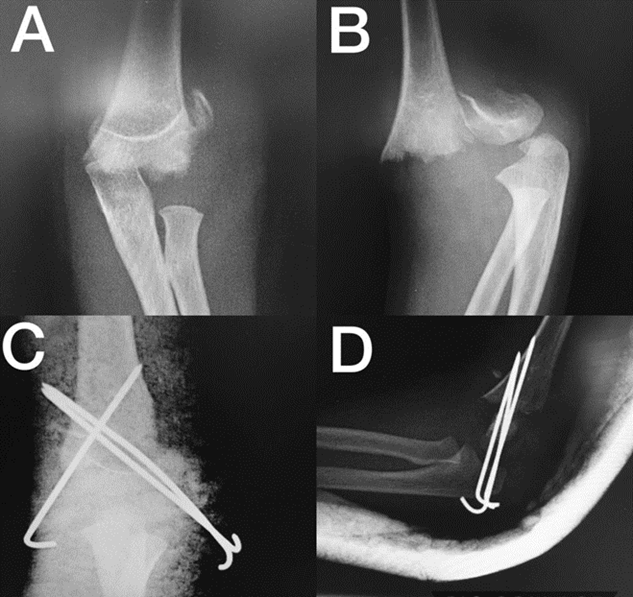

Luego se debe verificar la reducción en el fluoroscopio y proceder a la fijación con pines percutáneos32. Para ello se usan pines de Kirschner de 0.625 pulgadas. El número de pines depende del grado de inestabilidad, pero se acepta el uso de dos en las fracturas Gartland II y tres en las Gartland III y IV26. Por otro lado, la configuración de los pines es controversial, pues, aunque es cierto que la configuración cruzada da mayor estabilidad a la reducción, tiene mayor riesgo de injuria iatrogénica del nervio cubital. Sin embargo, hay estudios que demuestran que con una modificación en la técnica, se puede reducir ese riesgo33.

Siguiendo con la técnica quirúrgica, mientras se mantiene el brazo flexionado para conservar la reducción, el primer pin se inserta lateralmente de distal a proximal, lo más cerca posible a la línea media de la diáfisis del húmero, lateral al olécranon hasta llegar a la cortical medial del húmero, atravesando la línea de fractura. El segundo pin se inserta justo en el cóndilo lateral con el objetivo de que quede divergente al primero y atraviese la línea de fractura tan alejado del primer pin como sea posible, para que la reducción quede estable. Igualmente se avanza hasta que atraviese la cortical medial del húmero21.

También está descrita la configuración paralela de los pines, pero proporciona menor estabilidad a la reducción34. En caso de usar un pin medial, algunos recomiendan, una vez se haya puesto por lo menos un pin lateral para evitar la pérdida de la reducción, extender la extremidad para que el nervio cubital se desplace hacia la parte posterior (ya que con el miembro superior flexionado, el nervio se encuentra anterior, con mayor riesgo de ser lesionado) e insertar el pin por el epicóndilo medial, tan anterior como sea posible, para evitar lesionar el nervio. Sharma et al.35 no obtuvieron ni un solo caso de lesión iatrogénica del cubital en 30 de 90 casos que fueron manejados con pines cruzados, y determinaron que la estabilidad con pines laterales era comparable a la lograda a través de la configuración cruzada. Sin embargo, un metanálisis36 de 18 estudios encontró que el abordaje con pines cruzados cuadruplica el riesgo de injuria iatrogénica del cubital, mientras que la estabilidad es comparable con la de los dos pines laterales (en dicho metanálisis recomiendan el uso de dos pines laterales divergentes). En general, hay autores que siguen ambas corrientes, con mayor tendencia a la postura de pines laterales divergentes por el riesgo de la lesión iatrogénica del nervio cubital con la configuración cruzada37.

Para asegurar una estabilidad adecuada con la configuración cruzada, el pin medial debe atravesar la línea de fractura lo más alejado al pin lateral como sea posible (en caso de que solo un pin lateral haya sido usado) y llegar a la cortical lateral. Luego se doblan y se cortan los pines, dejando unos centímetros para facilitar su retiro. Se venda con un filtro estéril. Por último, se inmoviliza la fractura con férula posterior a 90° de flexión21,30.

En la Figura 9 se puede ver una fractura supracondílea Gartland IV y la reducción y fijación con 3 pines percutáneos, dos laterales y uno medial y en la Figura 10, una fractura supracondílea Gartland II con desplazamiento posteromedial con reducción cerrada, fijación percutánea con dos pines laterales e inmovilización con férula.